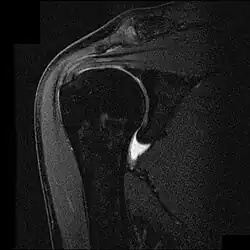

![]() Imagen por resonancia magnética nuclear mostrando el pinzamiento y ruptura parcial del tendón del músculo supraespinoso. | ||

En el caso de complementar con pruebas imagen, a menudo se utiliza la radiografía, el examen por ultrasonido y la resonancia magnética nuclear para confirmar la sospecha diagnóstica. La radiografía permite descartar que existan espolones o anomalías en la morfología del acromion que se hayan constituido como causa del síndrome, así como otras patologías identificables a través de esta prueba de imagen como la tendinitis calcificante, fracturas o neoplasias. El ultrasonido es una forma rápida, precisa y barata de evaluar posibles roturas parciales del manguito.[13] Sin embargo, dentro de las pruebas radiológicas, la resonancia magnética nuclear se considera el gold standard para evaluar roturas parciales o totales de los tendones afectados, aunque un estudio halló que esta solo se realiza en el 5,2% de los sujetos afectados.[14]